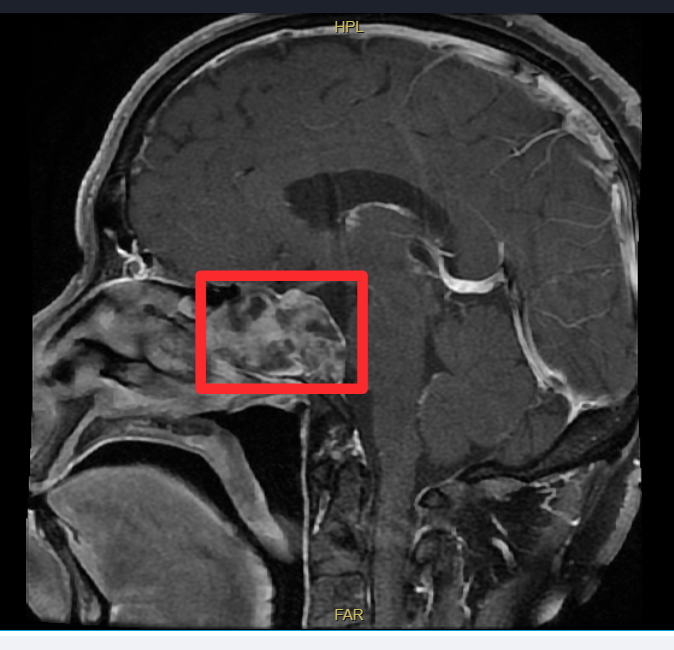

陈先生来到了中大医院,找到了孙宝宾副主任医师。经过详细的术前检查和评估,孙宝宾副主任医师团队认为肿瘤很可能起源于颅底的蝶窦区域,并已对周围骨质造成了侵蚀。为明确肿瘤性质,团队为其实施鼻内镜下蝶窦肿物活检术。术后病理报告确诊为脊索瘤。

经过周密的术前准备,一场在生命禁区「绣花」的手术开始了。孙宝宾副主任医师团队采用先进的鼻内镜微创技术,术中发现肿瘤充满蝶窦腔,起源于斜坡,呈胶冻状,已破坏窦底与斜坡骨质,甚至与深处的脑膜发生了粘连。每一步操作都如履薄冰,稍有不慎就可能引发大出血或神经损伤。

凭借对鼻颅底解剖结构的深刻认知与娴熟内镜操作技巧,孙宝宾副主任医师先开放手术通道、充分暴露肿瘤,再细致剥离肿瘤组织与重要脑膜结构,随后整块切除肿瘤,并以等离子烧灼干净肿瘤基底部。术中脑膜未破裂,为术后恢复奠定坚实基础。